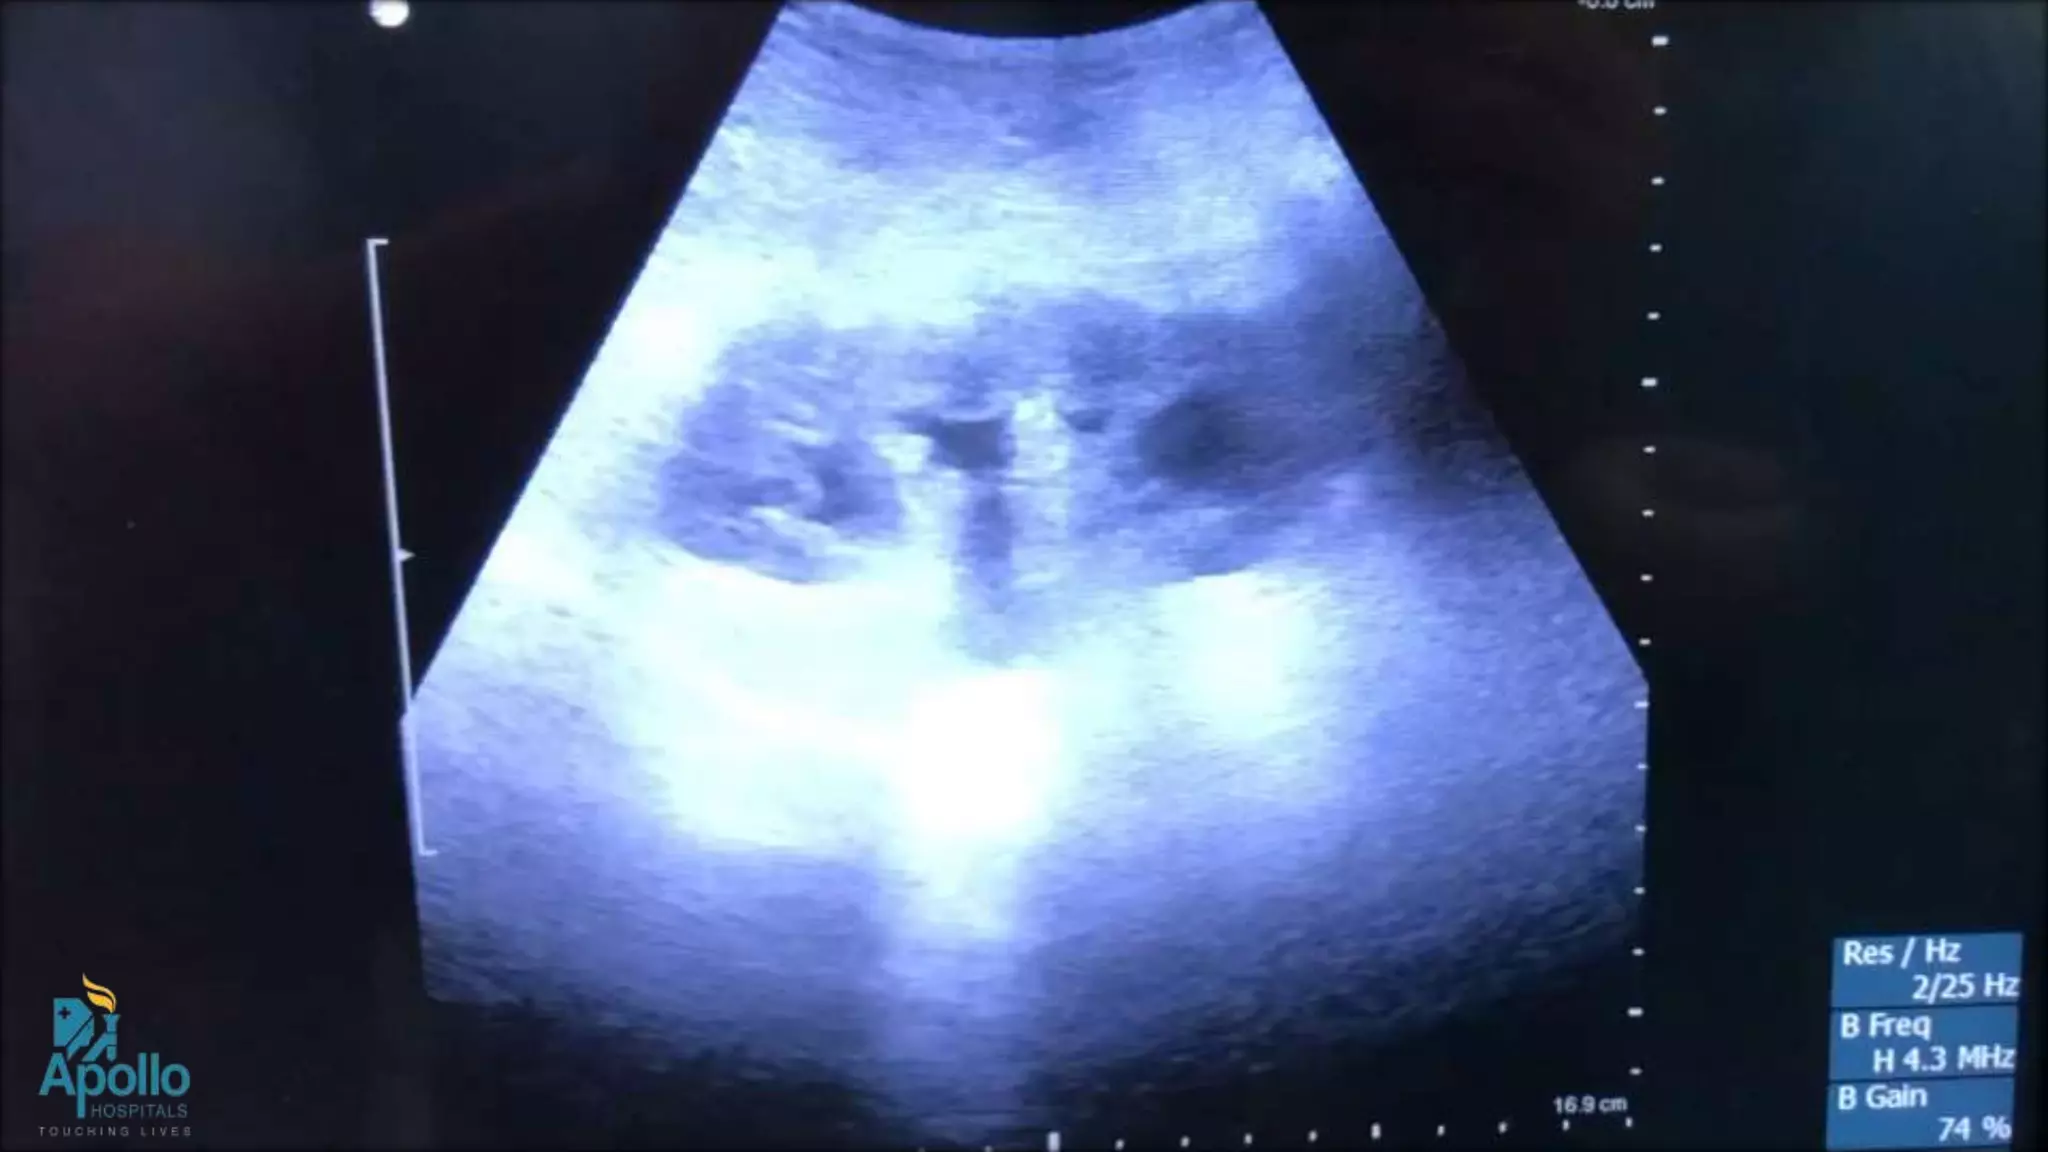

USG guided Percutaneous Nephrostomy

(Fluroless) – Tips and Tricks

• Can be done Fluroscopy, USG, CT guided

• USG guided PCN can be done in both Prone or supine, but probably

prone is easier

• USG “Guide” if available is helpful but not necessary

• Convex probe are useful

• Diamond tip needle are better than bevelled one

• Use jerky movement to see the movement of the kidney and

direction of the needle

• Once inside the PCS , can instill contrast if fluoroscopy is available to

complete the procedure